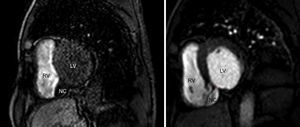

The echocardiogram revealed interventricular septal rupture with an extensive interventricular communication at the level of the posterobasal septum, associated with a serpiginous dissection of the septum, forming a neocavity, with an exit port in the mid-apical area of the right ventricle (Figure 1). Akinesis of the basal half of the inferior and posterior wall was also evident.

Transthoracic echocardiography, subcostal (left) and apical 4-chamber view, zoom on the left ventricle (right). Rupture of the interventricular septum, with septal dissection. LA: left atrium; LV: left ventricle; NC: neocavity formed by the dissection of the interventricular septum; RA: right atrium; RV: right ventricle. Arrow: interventricular septal rupture.